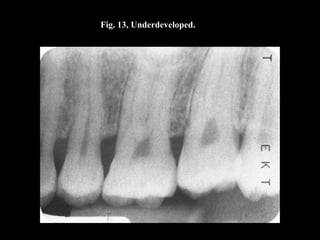

Fig. 13, Underdeveloped.